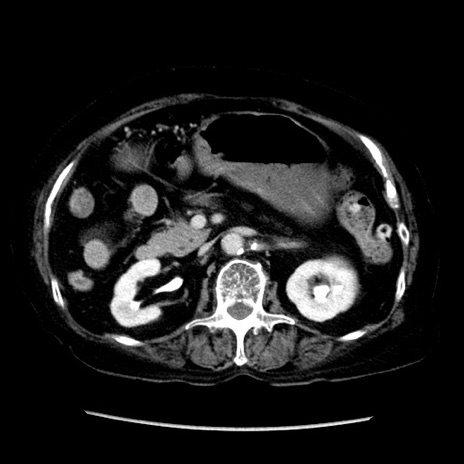

症例14(横断像)

【症例】 90歳代女性

【主訴】 腹痛・嘔吐

【現病歴】今朝から左側腹部痛を認めた。 経過観察していたが、嘔吐を認めたため来院。

【既往歴】 子宮癌術後

【身体所見】 意識清明、BP 127/54mmHg、P 98bpm Sp02 95%(RA)、BT 35.8°C、腹部平坦・軟腸ぜん動音聴取良好、右下腹部圧痛(+) 反跳痛なし

【データ】WBC 9800、CRP 0.46